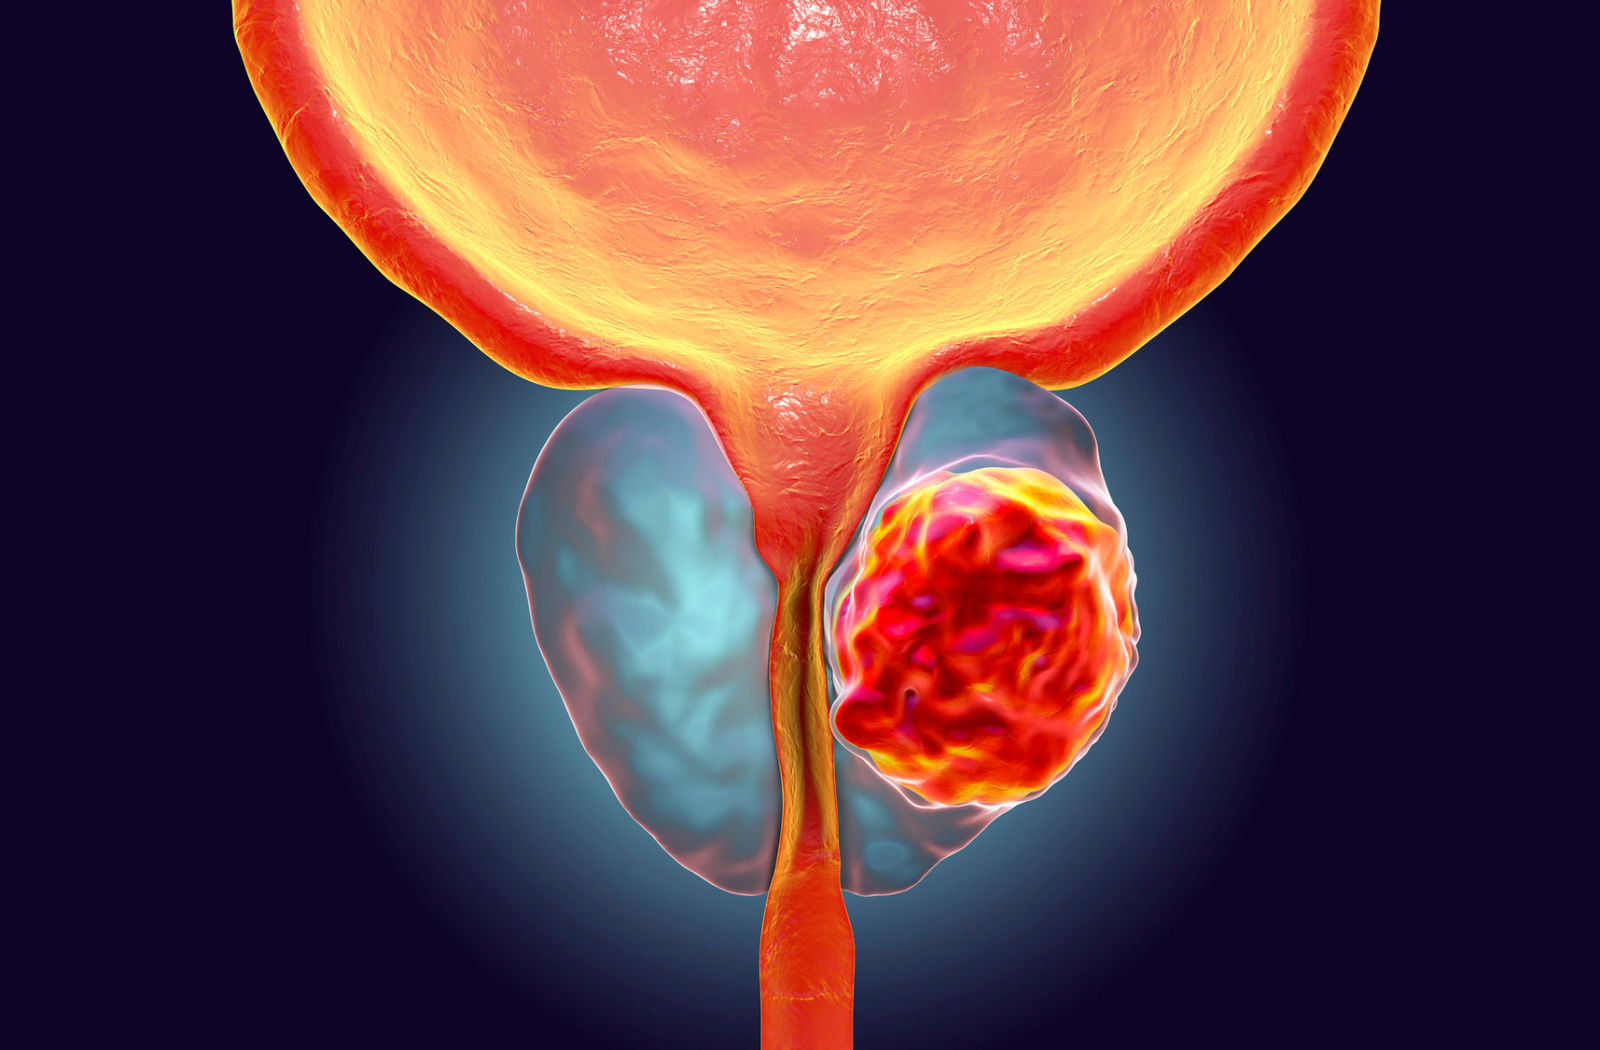

- Câncer de próstata

A cirurgia robótica é a mais moderna técnica cirúrgica utilizada em procedimentos urológicos, oferecendo alta precisão e menos invasividade. Com o auxílio do sistema robótico, o cirurgião tem visão ampliada em 3D e movimentos mais delicados, proporcionando resultados superiores.

Principais indicações: